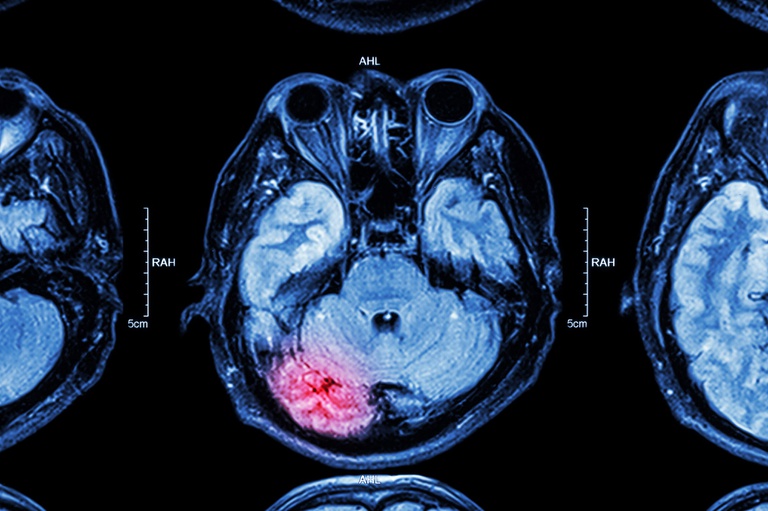

Prevenção pode evitar 90% dos casos, o que motiva a divulgação de informações sobre a doença, seus fatores de risco, tratamento e necessidade de reabilitação multiprofissional precoce

Uberlândia (MG) – O Acidente Vascular Cerebral (AVC) é a segunda causa de morte e a primeira de incapacidade no Brasil. De acordo com os especialistas, a prevenção pode evitar 90% dos casos. Por isso a importância da divulgação de informações sobre a doença, seus fatores de risco, tratamento e necessidade de reabilitação multiprofissional precoce.